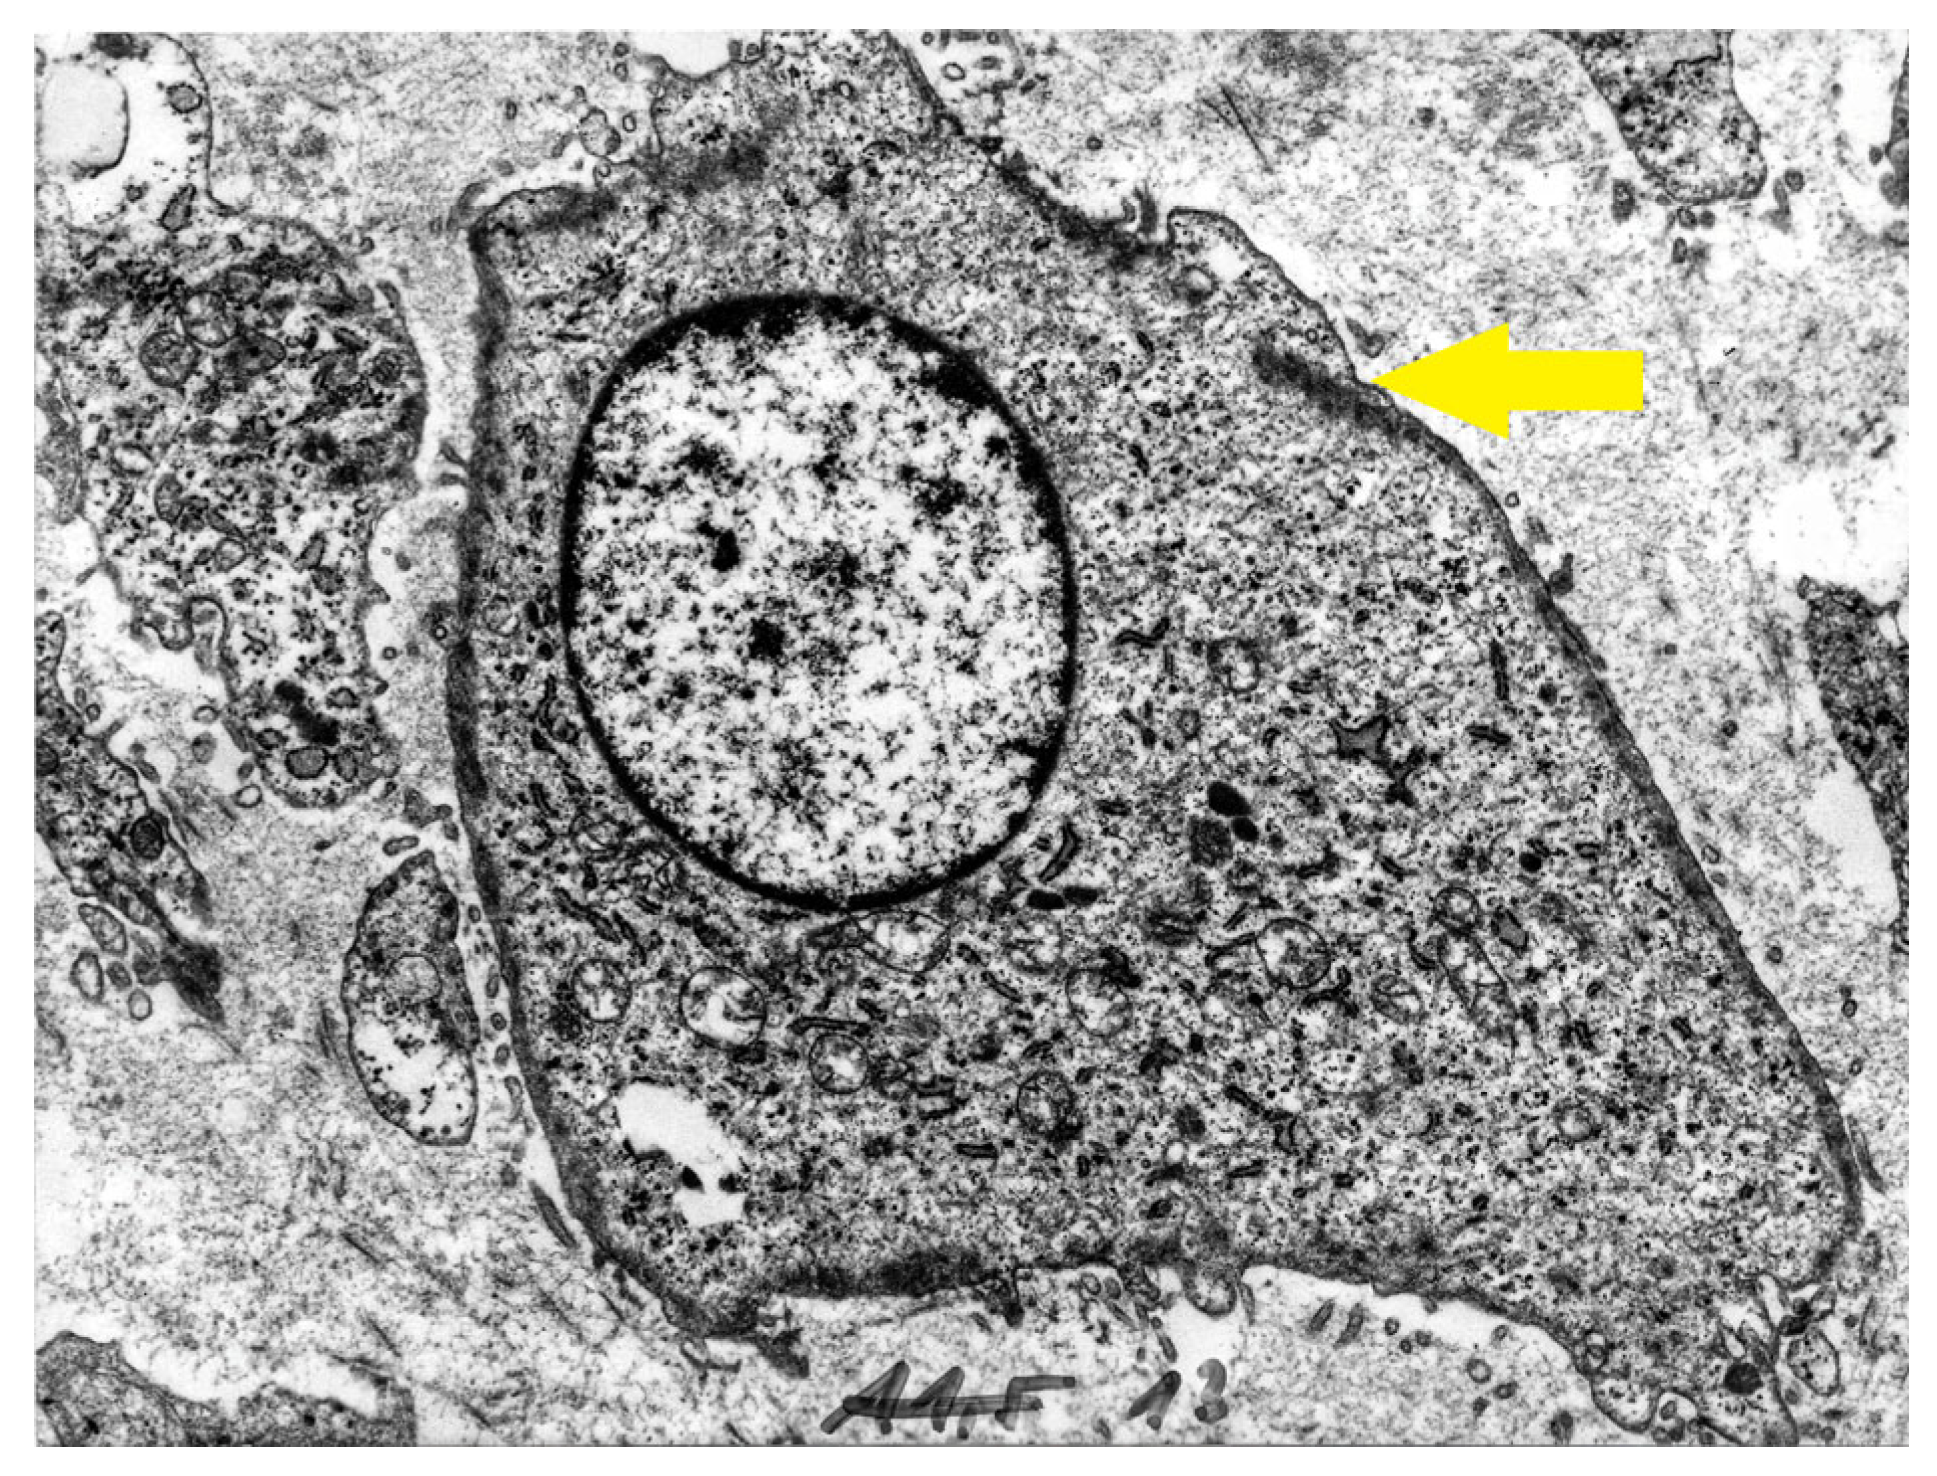

2.2.1. Auricular Cartilage

2.2.2. Myochondrocytes in Normal Articular Cartilage